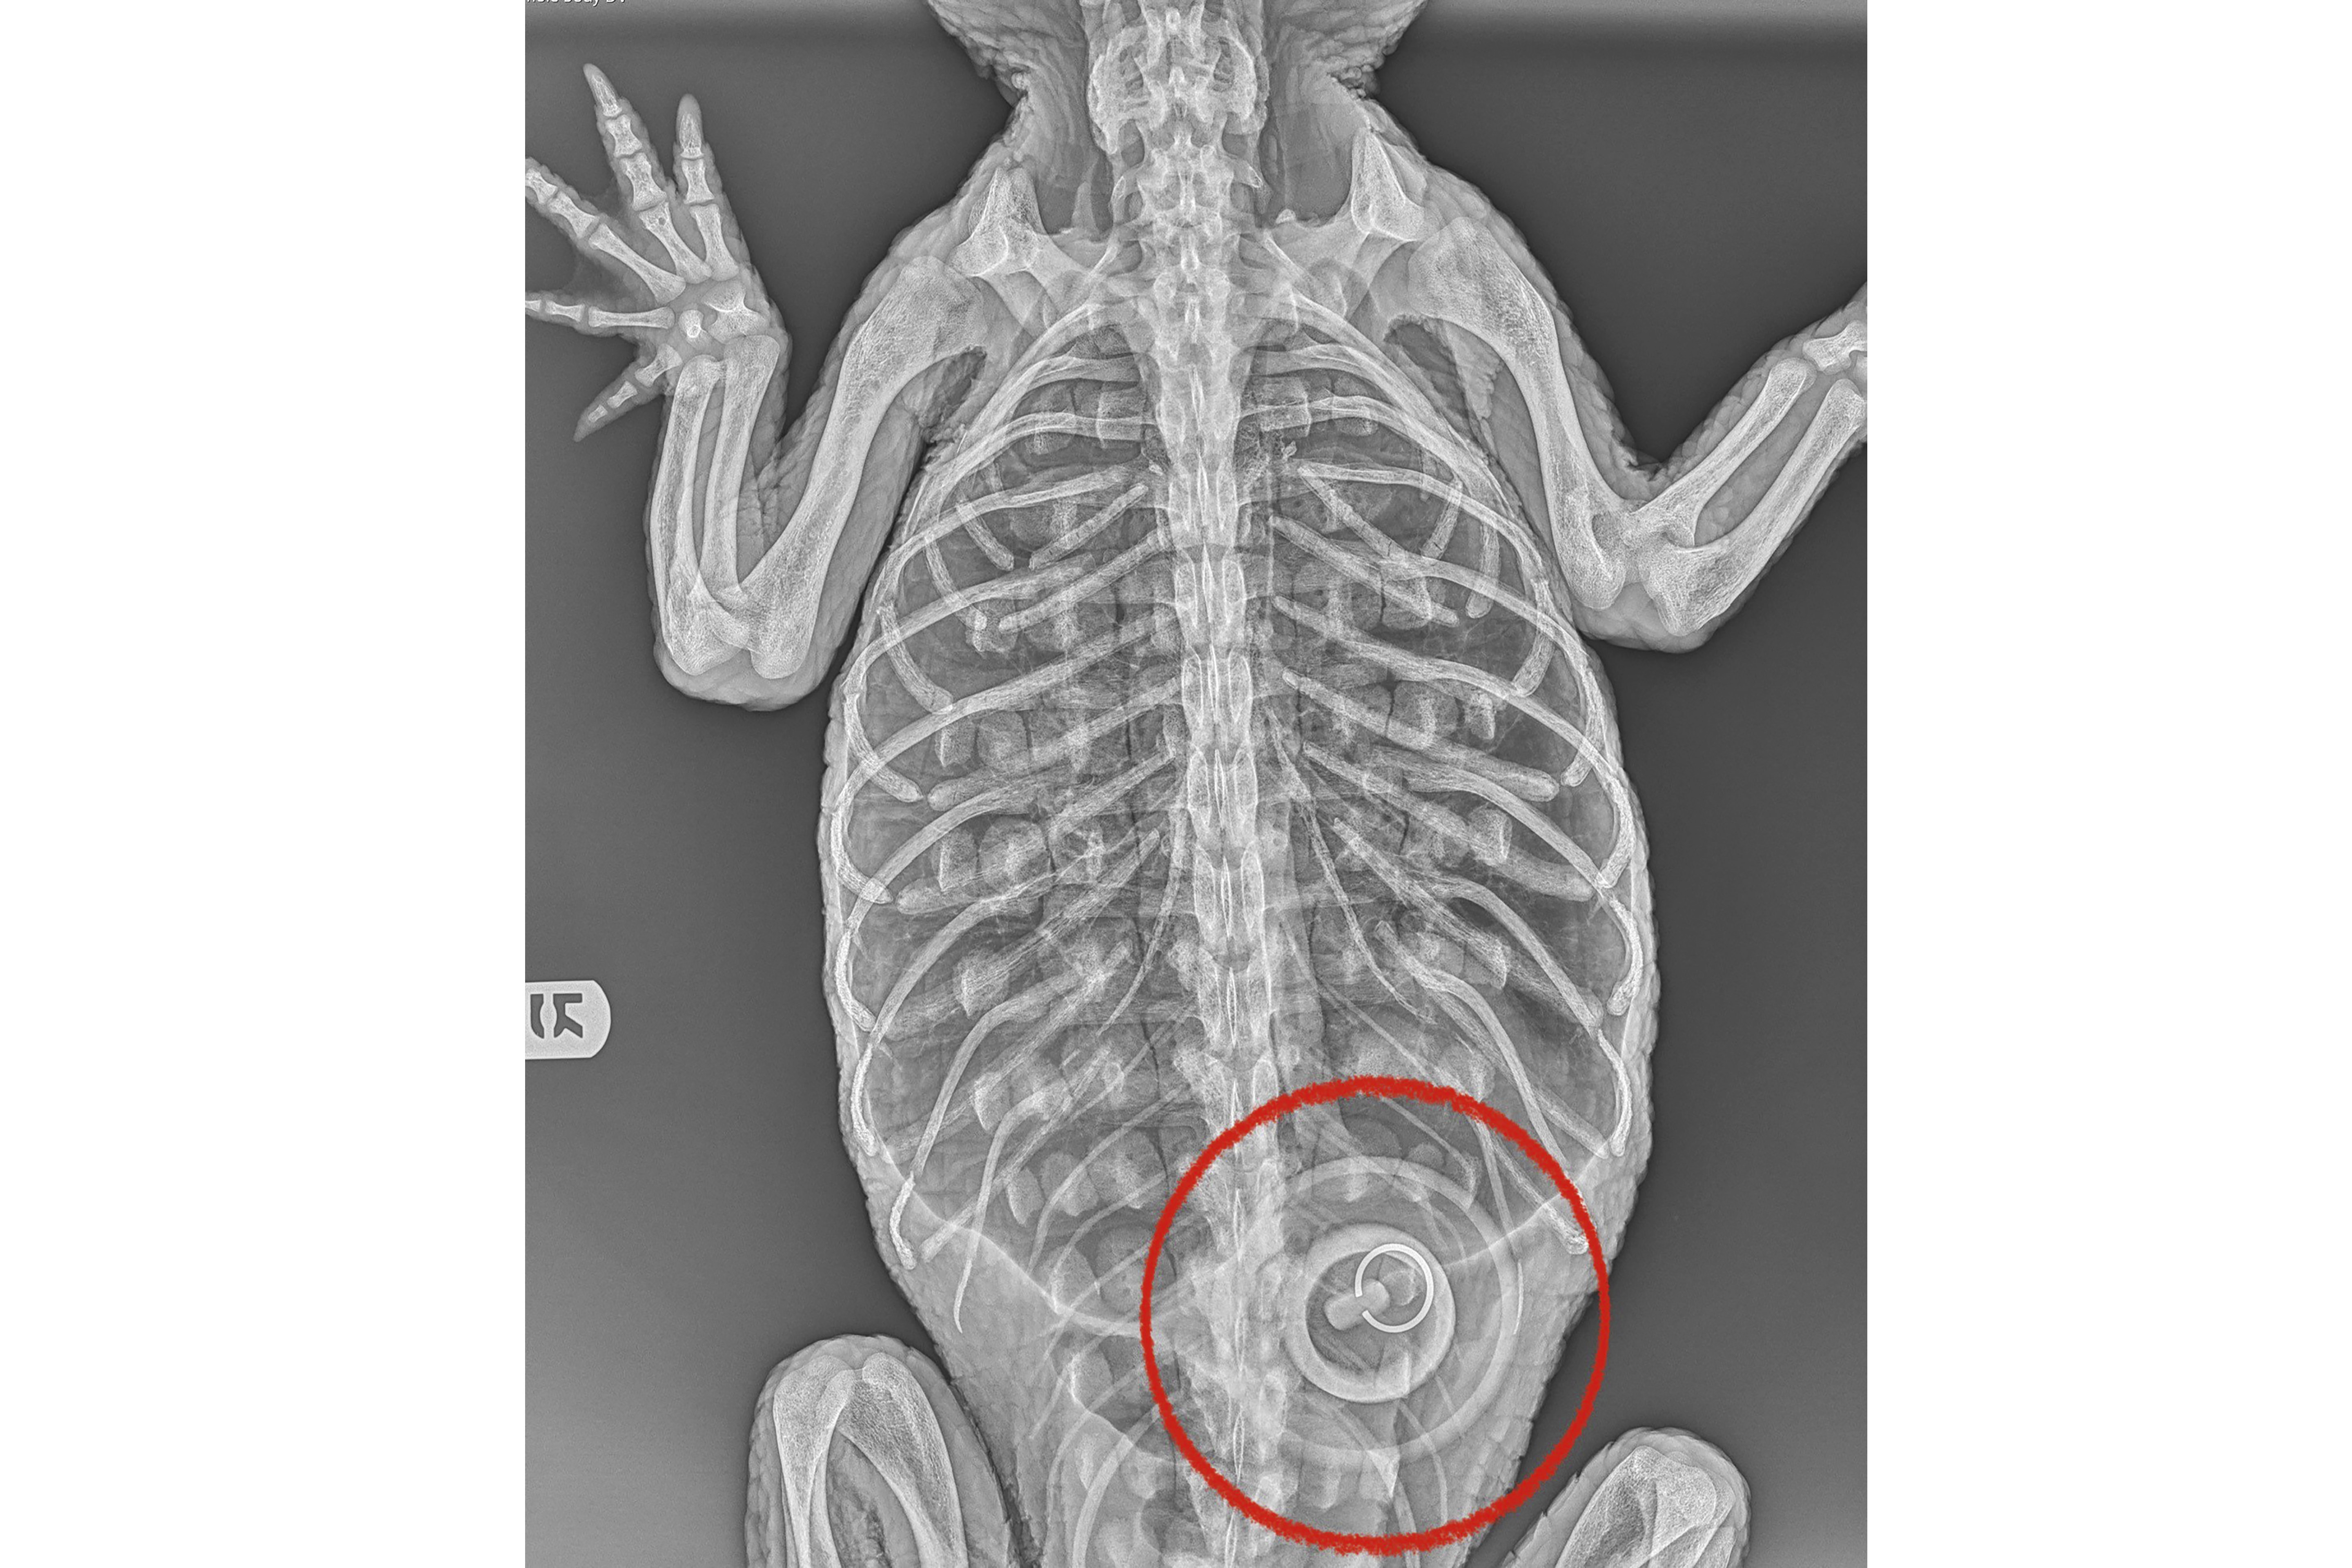

X-rays show that the alligator, estimated to be 5 to 6 years old, had ingested a 4-inch bathtub stopper, zoo officials said, noting that the animal is too weak for veterinarians to try to remove it.